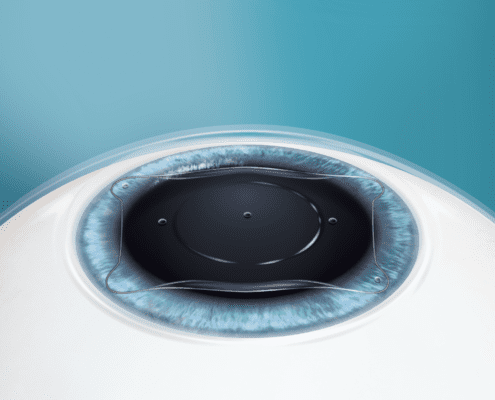

Refractive Surgery

The specialists at Parker Cornea work to provide you with the best vision possible through a wide variety of refractive surgery options, including implantable collamer (contact) lenses, refractive lens exchange / clear lens extraction, and pinhole pupilloplasty.